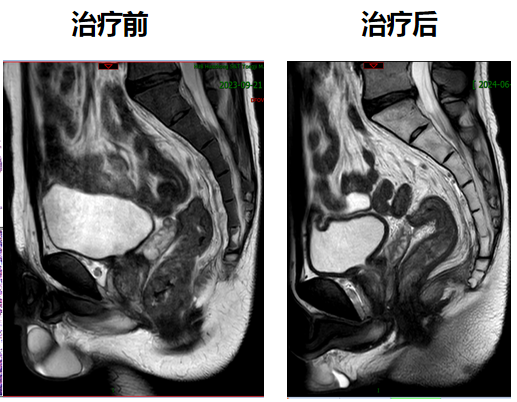

今年33岁的小江(化名)是接受该创新治疗模式的患者之一。2023年9月,小江在协和医院确诊为低位直肠腺癌T3N2M0,肿瘤下缘距离肛门口仅2厘米,保肛难度确实非常大。

经过胃肠外科、腹部肿瘤科、影像科、病理科等多学科讨论后,最终决定采用短程放疗序贯化免联合全新新辅助治疗。2023年9月,小江接受了5次直肠病灶及淋巴结引流区放疗,随后进行化疗联合免疫新辅助治疗。今年1月,再次复查肠镜发现,他的直肠下段肿瘤病灶已经消失,获得了临床完全缓解。这也意味着小江的肿瘤术前完全消退,后续接受规范的监测和复查即可。